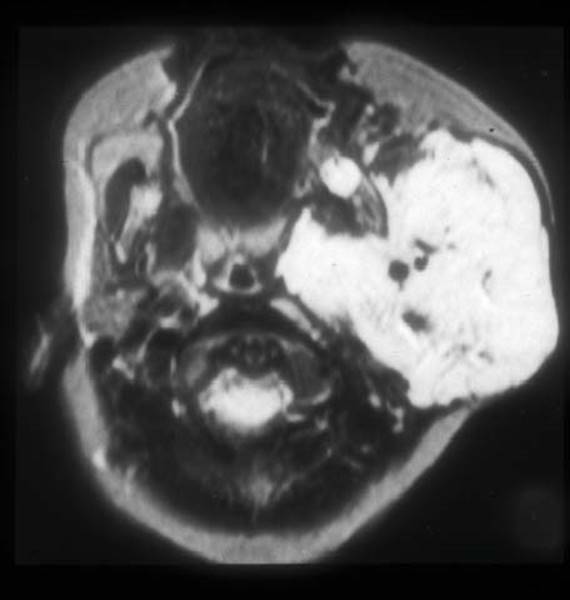

Imaging

Imaging of preschool age children with extensive neck and airway hemangiomas may require sedation and endotracheal intubation. CT scan of the neck with contrast provides good tissue detail. MRI or magnetic resonance angiography is helpful in defining the extent of the lesion and its vascularity. The diagnostic findings of hemangiomas on T2-weighted MRI are multiple septated lobules of high signal intensity resembling a “bunch of grapes” (Fig. 19.10).25 Thrombosis appears as circular areas of low signal intensity similar to phleboliths.

Figure 19.10 Magnetic resonance image of large neck (parotid) hemangioma.